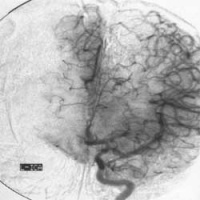

脑动脉造影[编辑 | 编辑源代码]

脑动静脉畸形有以下典型表现:①显示畸形血管。这是特征表现,呈一团管径相仿相互纠缠的迂曲扩张血管。畸形血管团的范围可小如指甲,大如手掌,多见大脑半球皮质.②异常粗大的供养动脉和引流静脉伴局部循环加快。此为局部血流短路的表现。③血流分流现象:造影剂随血流经畸形血管的短路大量流入静脉,因此,血管畸形部分因血流量增加而显影十分清楚。④血肿的表现:血管破裂出血致脑内血肿,血肿的主要表现为局部占位征象,一股脑部动静脉畸形无血肿时,脑血管不出现占位征象,脑血管不移位。

5.脑血管造影:最可靠、最重要的诊断方法,动脉期可见血管团、供血动脉及早期显现的引流静脉。

4、脑血管造影是本病最可靠和主要的诊断方法,并能行血管内介入治疗。

1、由于有多发的可能,术前应作全脑血管造影或双侧颈动脉造影,或按畸形血管部位推测,加作椎动脉造影。典型的脑动静脉畸形包括供应动脉、畸形灶及引流静脉三部分。通过造影应查清供应动脉来源及引流静脉走向,畸形灶的部位及范围,有无血肿等合并症,以及病人有无它处畸形。才能制订出完善的手术计划,也是手术成功的关键。